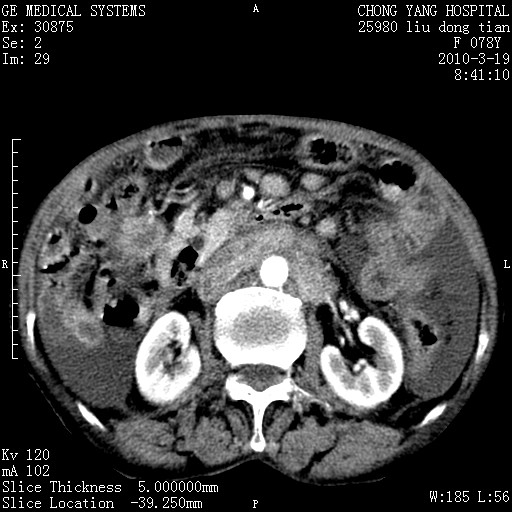

标题: CT25199:F 78Y 腹胀半年 消瘦乏力 [打印本页]

标题: CT25199:F 78Y 腹胀半年 消瘦乏力

胆囊壁增厚并明显强化,胆囊癌伴多发转移瘤可能性大,淋巴瘤不除外,右肾囊肿,胸腹水.

考虑nhl,肝、脾、腹膜腔及腹膜后多发淋巴结受侵,腹水,右肾囊肿,慢性胆囊炎,右侧少量胸腔积液。

首先考虑恶性淋巴瘤 。

胰头有肿块形成,胰头ca伴肝脾、腹膜腹膜后转移

胆囊有软组织影有强化,支持胆囊癌,肝脾、腹膜后淋巴结转移。

nhl的淋巴结多围绕主动脉,而且主动脉会移位,所以不考虑nhl。

分开来讲:肝左叶、尾叶病灶有不均强化像肝癌;

脾脏病灶无强化,像多发囊肿或淋巴管瘤,不除外淋巴瘤(低强化);

胆囊增生性病变:胆囊癌,腺肌增生症,慢性胆囊炎;

肝门、胰腺头、腹膜后多个团块: 淋巴瘤,转移;

腔静脉肝内段细小有无布加可能?

一元论最好了 淋巴瘤所致改变; 胆囊癌转移不像,胆囊周围肝组织清晰,肝癌淋巴结转移?三元论都不止。

胰头ca伴肝脾、腹膜腹膜后转移!

最后报的胰头癌多发转移,脾脏单独考虑囊肿或淋巴管瘤。